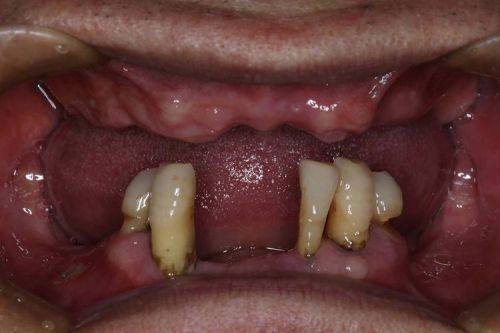

种植牙项目

| 半口All - on - 4(韩系) | 39800元起 |

| 全口All - on - 6(瑞士) | 78000元起 |